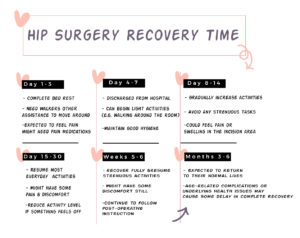

What Does the Hip Surgery Recovery Time Look Like for the Elderly?

The recovery process after hip surgery will vary depending on the type of surgery. For example, a hip replacement usually requires a longer recovery than a hip repair. One may need six months to a year to fully recover from hip surgery. Here’s the full timetable for hip surgery recovery for the elderly:

Day 1-3

You will likely be instructed to rest and keep your leg in an elevated position. You may also be given assistive devices like crutches or walkers to help you get around. Since you are expected to feel severe pain post-surgery, some pain medications might be given to subside it.

Day 4-7

If everything is under control, you will probably be discharged from the hospital and can begin light activities, such as walking around the house or room. Make sure to take it easy and avoid putting too much stress on your hip. It is also crucial to maintain good hygiene and keep the surgical area

Day 8-14

You can gradually increase your activity level, but continue avoiding strenuous exercises. At this time, you may continue to experience pain or swelling in the incision area as the wound is still tender. Also, by this time, your stitches should dissolve but if not, consider getting them removed.

Day 15-30

You can resume most of your everyday activities, but make sure to take it easy and listen to your body. If you experience any pain or discomfort, reduce your activity level until the pain subsides and consult with your doctor.

Weeks 5-6

You are expected to fully recover and resume strenuous activities in six weeks. However, you are still likely to have some pain and discomfort. Be sure to continue to follow your doctor’s post-operative instructions carefully.

Months 3-6

Most patients are expected to return to their normal lives after three to six months post-surgery. However, some elderly patients may take longer to make a full recovery due to age-related complications or underlying health issues such as diabetes or arthritis.

Hip Surgery Recovery Timeline